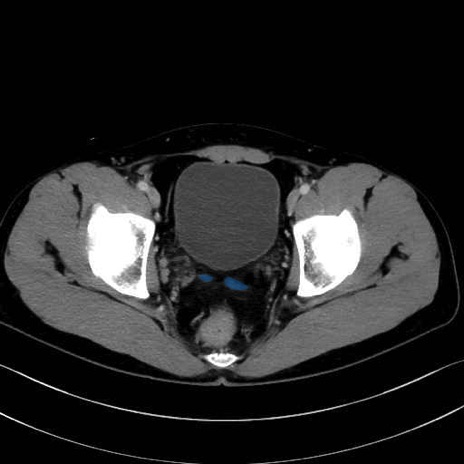

精嚢(seminal vesicle)のCT画像における解剖

症例

【症例】20歳代 男性 スクリーニング